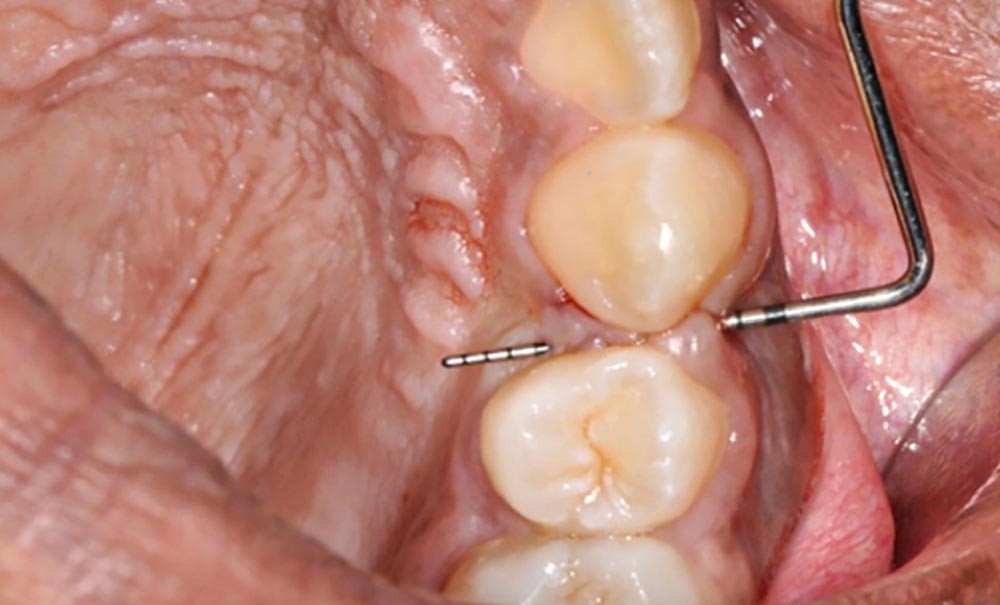

Au total, 23 patients ayant achevé leur traitement orthodontique au moins 3 mois auparavant ont été recrutés au sein de la structure interne d’Orthopédie Dento-Faciale des Hôpitaux Universitaires de Strasbourg. Nous avons étudié les caractéristiques de 70 sites d’avulsions au total. La présence ou l’absence de fente ainsi que les caractéristiques parodontales de chaque site ont été relevées (biotype gingival, indice de plaque, indice de saignement au sondage, hauteur de gencive attachée). La sévérité des fentes a été caractérisée à l’aide de l’indice de Reichert [6]. Des données concernant le déroulement et la durée du traitement orthodontique ont été recueillies rétrospectivement dans les dossiers des patients. Ces mêmes paramètres ont également été testés afin d’évaluer une possible association avec la sévérité de la fente (fig. 2).